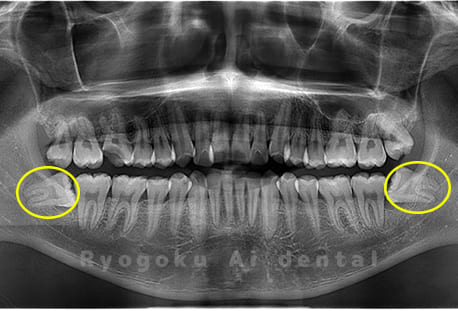

斜めに生えている親知らず

親知らずが斜めに生えて隣の歯にぶつかって圧迫してしまうタイプです。

このタイプが最も多いです。このタイプは虫歯になりやすいだけでなく、隣の歯を圧迫し、咬み合わせや歯並びに影響が出る場合もあるので抜歯をおすすめします。